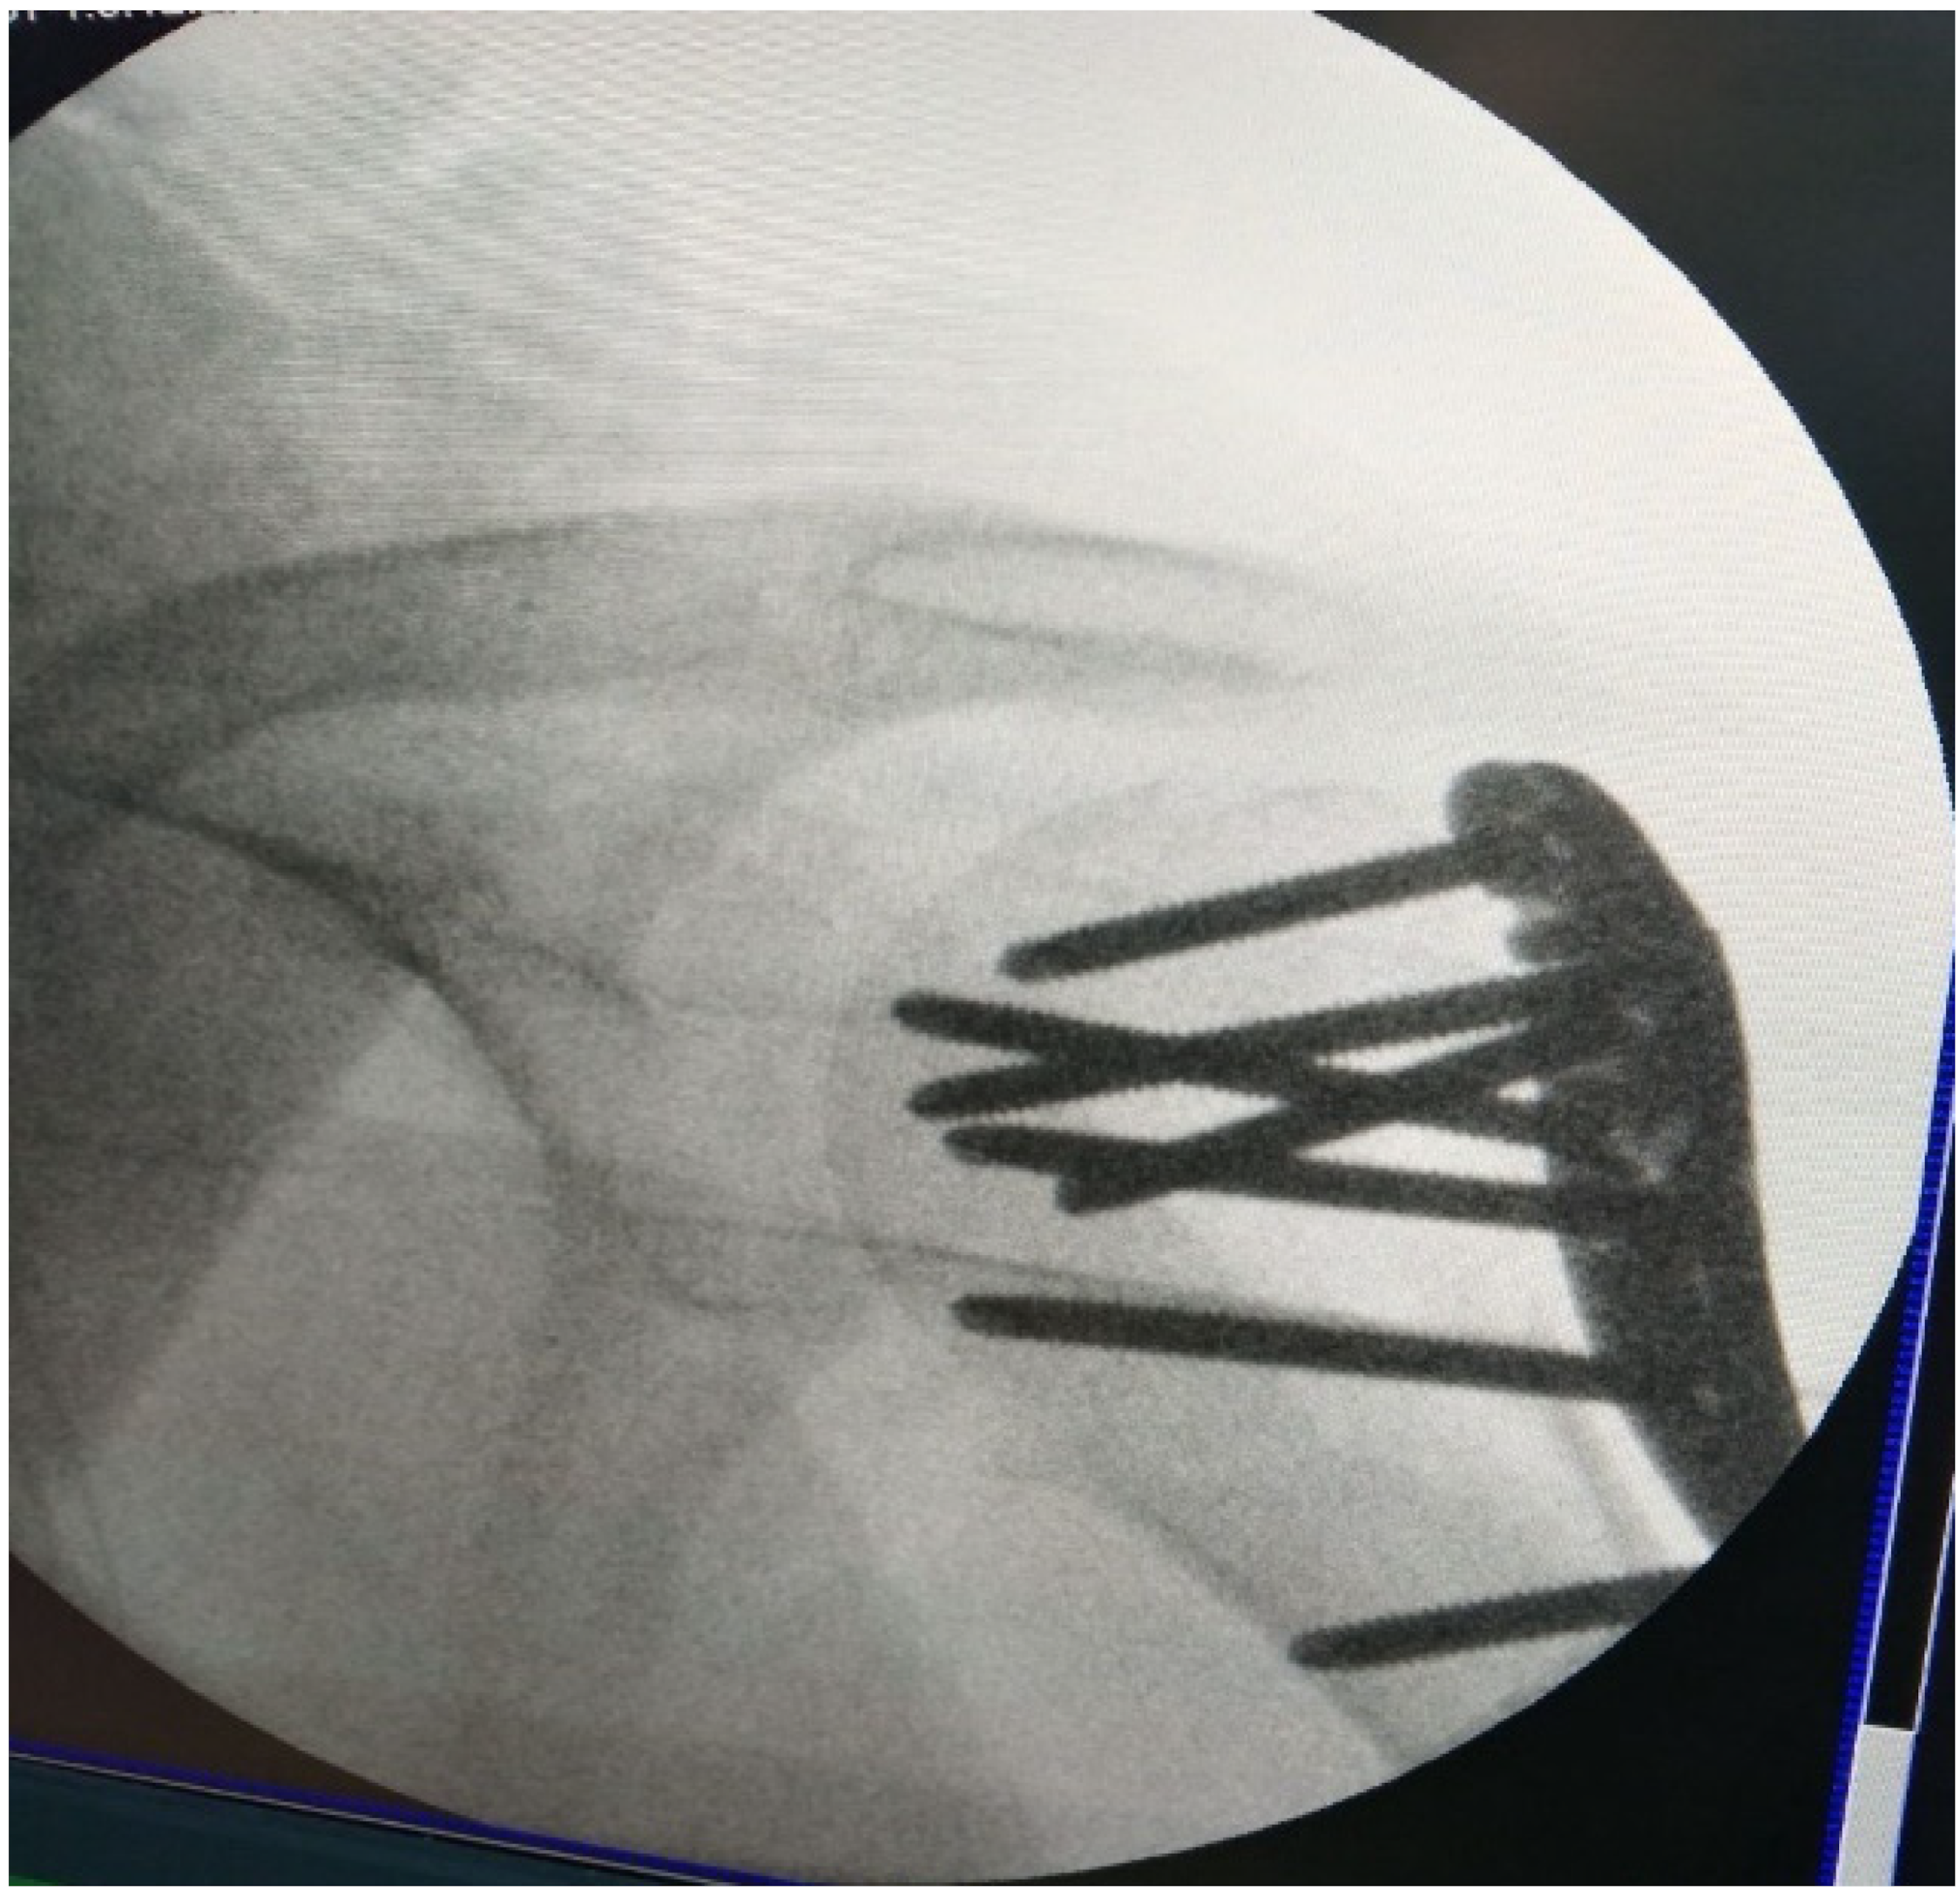

2.4. Treatment Modalities

2.2. Imaging Studies